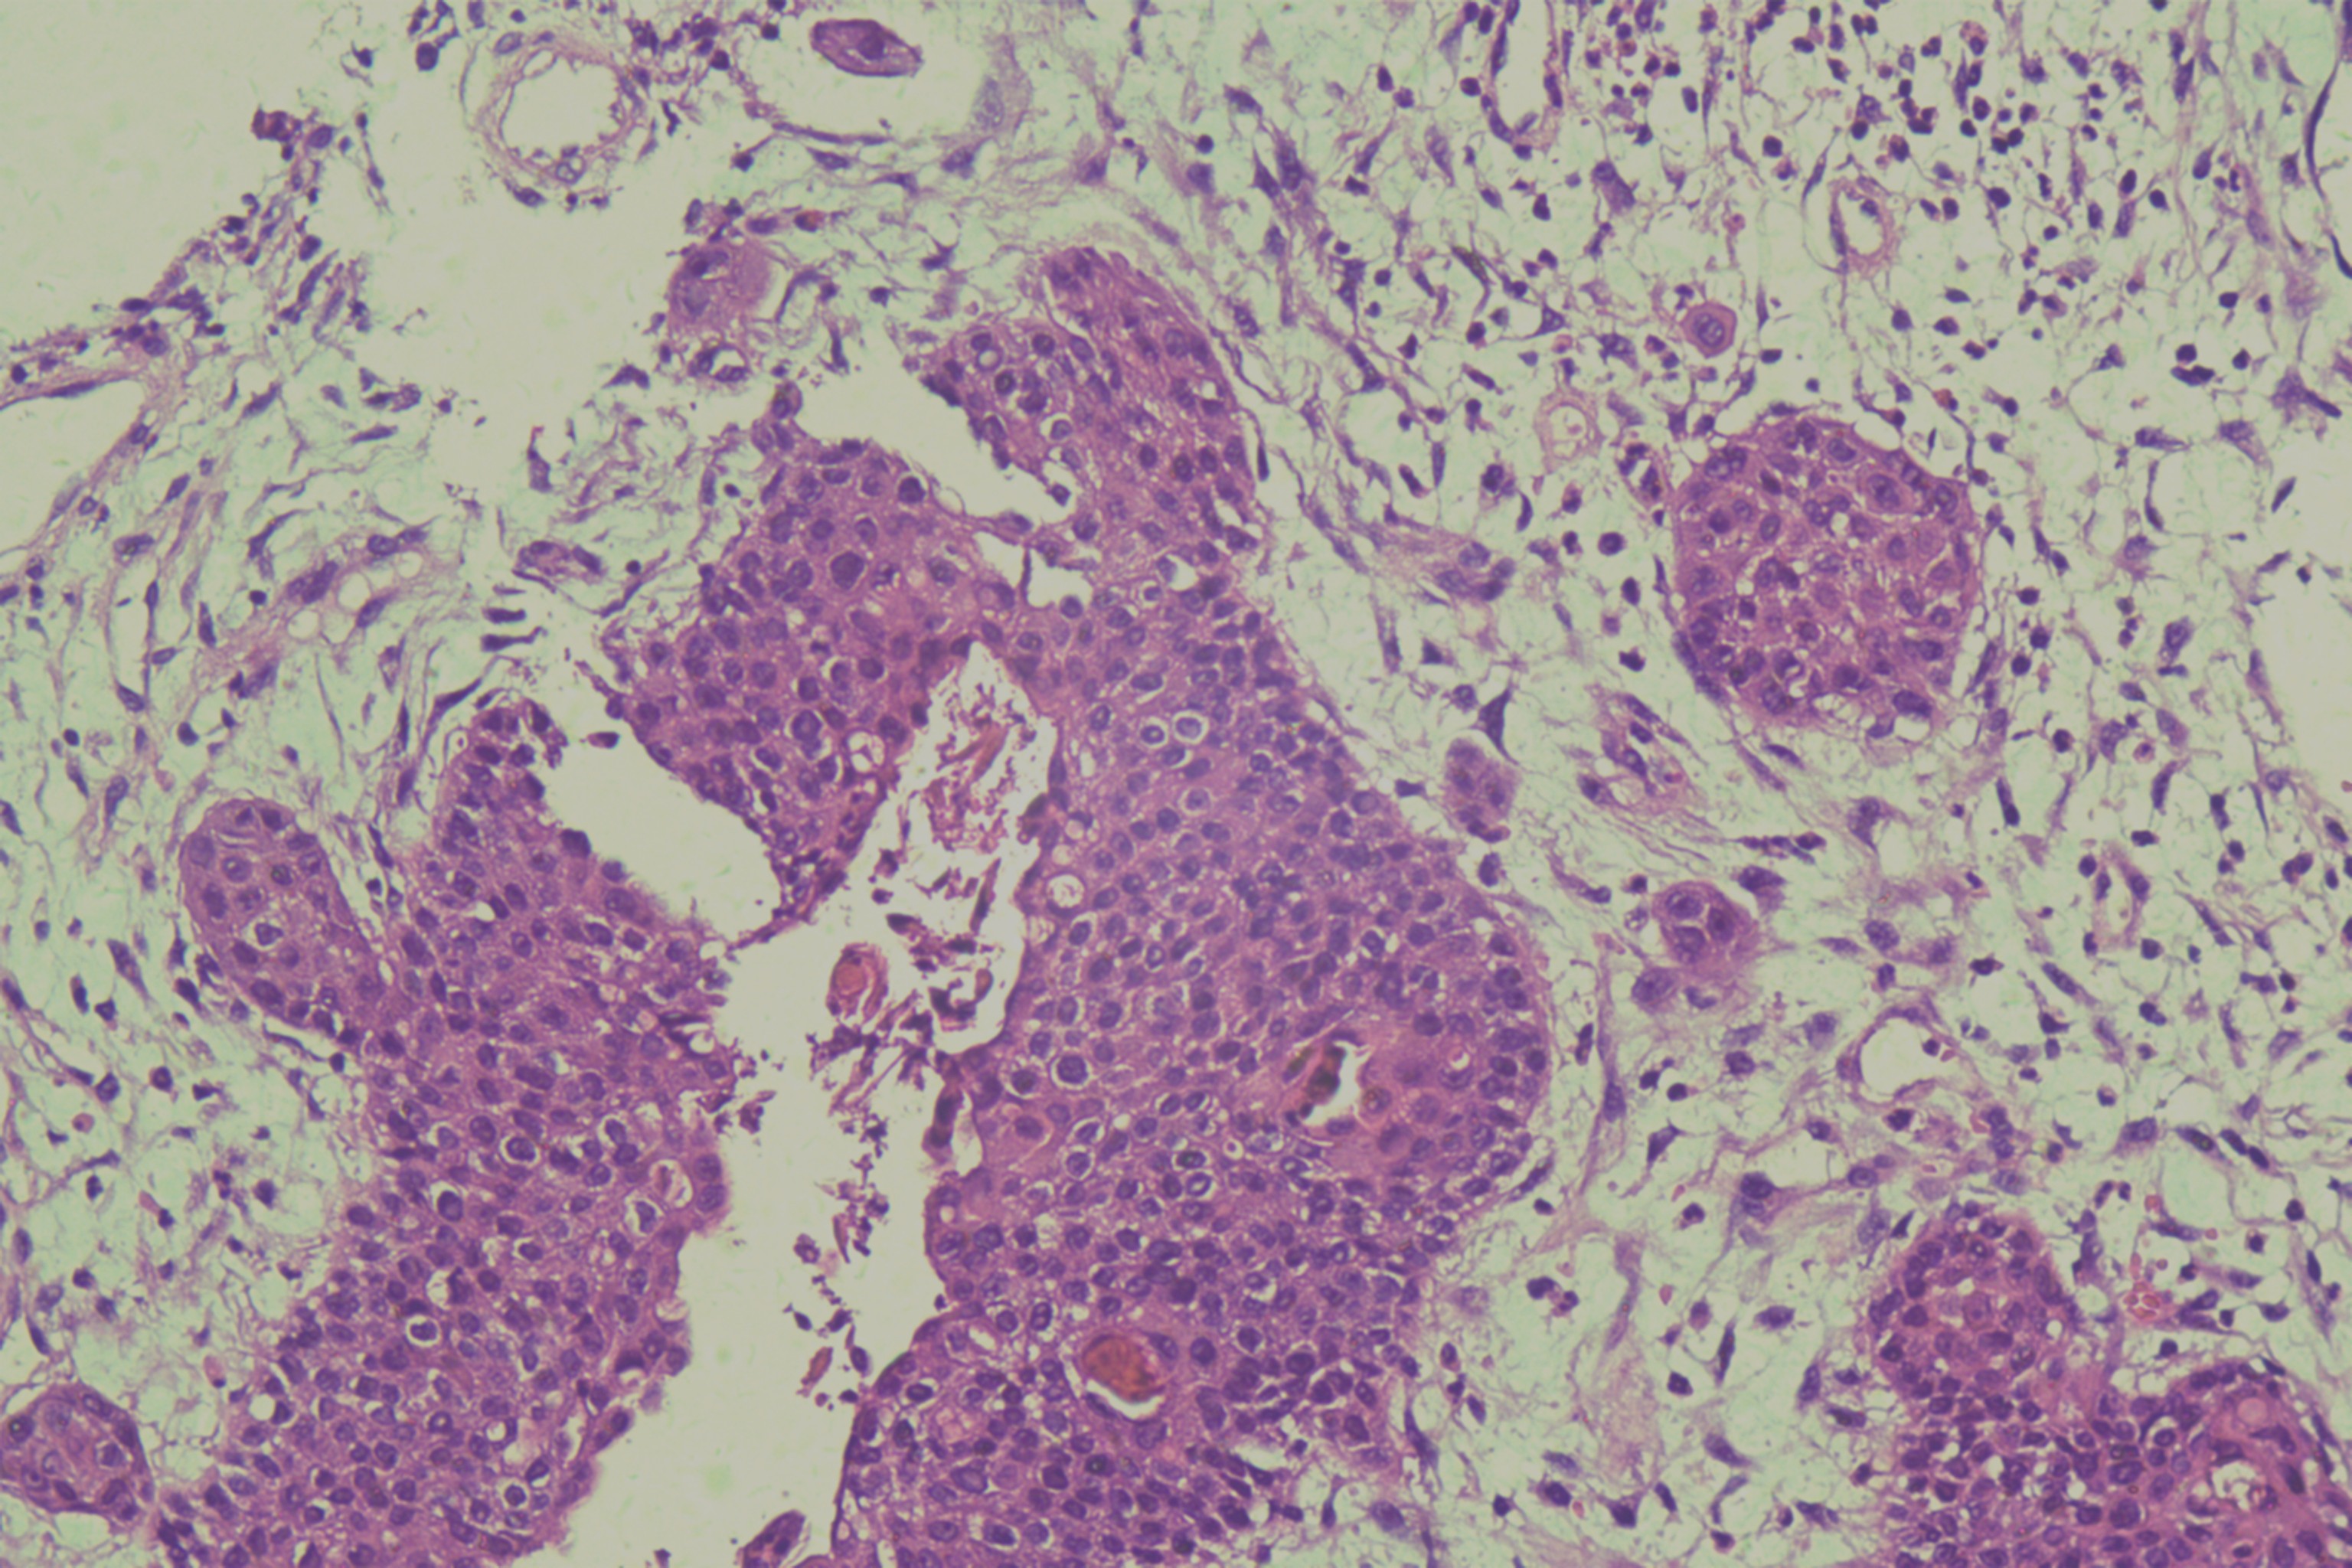

鳞癌?

性别

男

年龄

68岁

头皮肿物20年,包块逐渐增大,反复破溃

头皮肿物(局部活检)

1.5*1*0.3cm灰红碎组织一堆

考虑:基底细胞癌